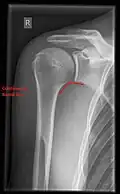

Fracture

Fractures of shoulder bones can include clavicular fractures, scapular fractures, and fractures of the upper humerus.

Imaging

Imaging of the shoulder includes ultrasound, X-ray and MRI, and is guided by the suspected diagnosis and presenting symptoms.

Conventional x-rays and ultrasonography are the primary tools used to confirm a diagnosis of injuries sustained to the rotator cuff. For extended clinical questions, imaging through Magnetic Resonance with or without intraarticular contrast agent is indicated.

Hodler et al. recommend starting scanning with conventional x-rays taken from at least two planes, since this method gives a wide first impression and even has the chance of exposing any frequent shoulder pathologies, i.e., decompensated rotator cuff tears, tendinitis calcarea, dislocations, fractures, usures, and/or osteophytes. Furthermore, x-rays are required for the planning of an optimal CT or MR image.[25]

X-ray

Projectional radiography views of the shoulder include:

- AP-projection 40° posterior oblique after Grashey

The body has to be rotated about 30 to 45 degrees towards the shoulder to be imaged, and the standing or sitting patient lets the arm hang. This method reveals the joint gap and the vertical alignment towards the socket.[26]

- Transaxillary projection

The arm should be abducted 80 to 100 degrees. This method reveals:[26]

- The horizontal alignment of the humerus head in respect to the socket and the lateral clavicle in respect to the acromion

- Lesions of the anterior and posterior socket border, or of the tuberculum minus

- The eventual non-closure of the acromial apophysis

- The coraco-humeral interval

- Y-projection

The lateral contour of the shoulder should be positioned in front of the film in a way that the longitudinal axis of the scapula continues parallel to the path of the rays. This method reveals:[26]

- The horizontal centralization of the humerus head and socket

- The osseous margins of the coraco-acromial arch and hence the supraspinatus outlet canal

- The shape of the acromion

This projection has a low tolerance for errors and, accordingly, needs proper execution.[26] The Y-projection can be traced back to Wijnblath’s 1933 published cavitas-en-face projection.[27]